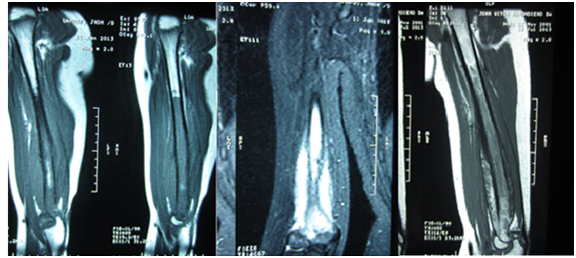

An 11-year-old male looked for medical assistance due to pain and swelling in his right arm, which had started three months earlier. Patient showed no other signs or symptoms. Swelling and warmth in the middle and distal thirds of the patient’s arm were found in physical examination. All laboratory tests fell within normal values, i.e., within reference range values, except for the LDH level, which was 280 U/L (normal LDH levels range from 100 U/L to 190 U/L). Radiological findings (Figures 1 & 2) showed permeable lytic lesions and “onion skin” periosteal reaction in the right humeral shaft. Thus, needle bone biopsy was indicated. Biopsy confirmed the presumptive diagnosis of Ewing’s sarcoma. After staging, which excluded the dissemination of the disease, the treatment protocol was started, which was neoadjuvant chemotherapy, associated to surgery and adjuvant chemotherapy. The oncologic resection procedure was performed 5 (five) months after the diagnosis - arthrotomy of the right elbow and humerus osteotomy at 22cm from the proximal extremity. In order to cover the bone defect, we opted for reconstruction with ipsilateral vascularized fibular autograft - a segment of 23cm of the right fibula with a vascular pedicle to the fibular artery has been resected. The medical team then performed a termino-lateral anastomosis to the brachial artery and termino-terminal anastomosis to the basilic vein (Figure 3). Clamping of the fibular graft under pressure in the humeral medullary cavity was the method of choice for graft fixation in the proximal end, and distally, the fixation was obtained with capsulorrhaphy of the head of the fibula to the elbow joint (Figure 4). The choice not to use a plate for proximal fixation was made in the intraoperative period due to the satisfactory stability obtained with the clamping of the graft in the humerus. Patient presented good postoperative evolution, with a satisfactory range of mobility in the limb which underwent surgery, and high patient-satisfaction ratings (Figure 5). Two fractures of the grafted bone segment (the first occurred 13 months after the surgery and the other one 32 months after the surgery) were the postoperative complications reported. Both of them were satisfactorily handled with conservative treatment, i.e., full cast.

Figure 1 Anteroposterior X-ray view of the right humerus and lateral view of the right elbow. Permeable lytic lesion and “onion skin” periosteal reaction in distal humerus can be seen.

Figure 2 MRI of the right humerus is useful to better evaluate the extent of the tumor and plan the surgical procedure. The medullar limit of the tumor is shown in the sagittal sequence on the left. The image to the right shows better definition of tumoral limits due to satisfactory response to chemotherapy.